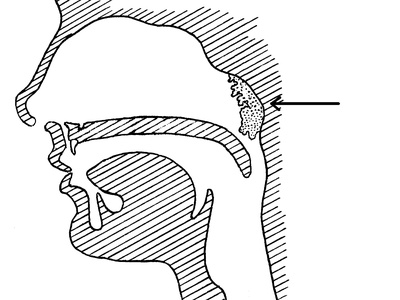

Adenoidectomy

Removal of adenoids (lymph tissue behind the nose) to treat chronic infections or breathing problems in children.